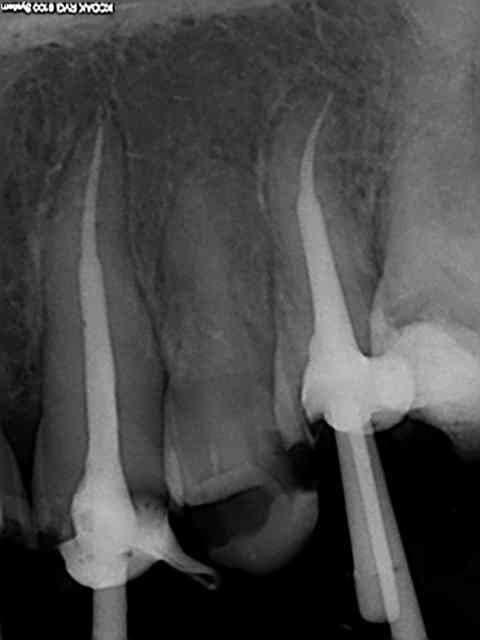

J'ai terminé la moitié de ma boite de gutta avec ce patient .